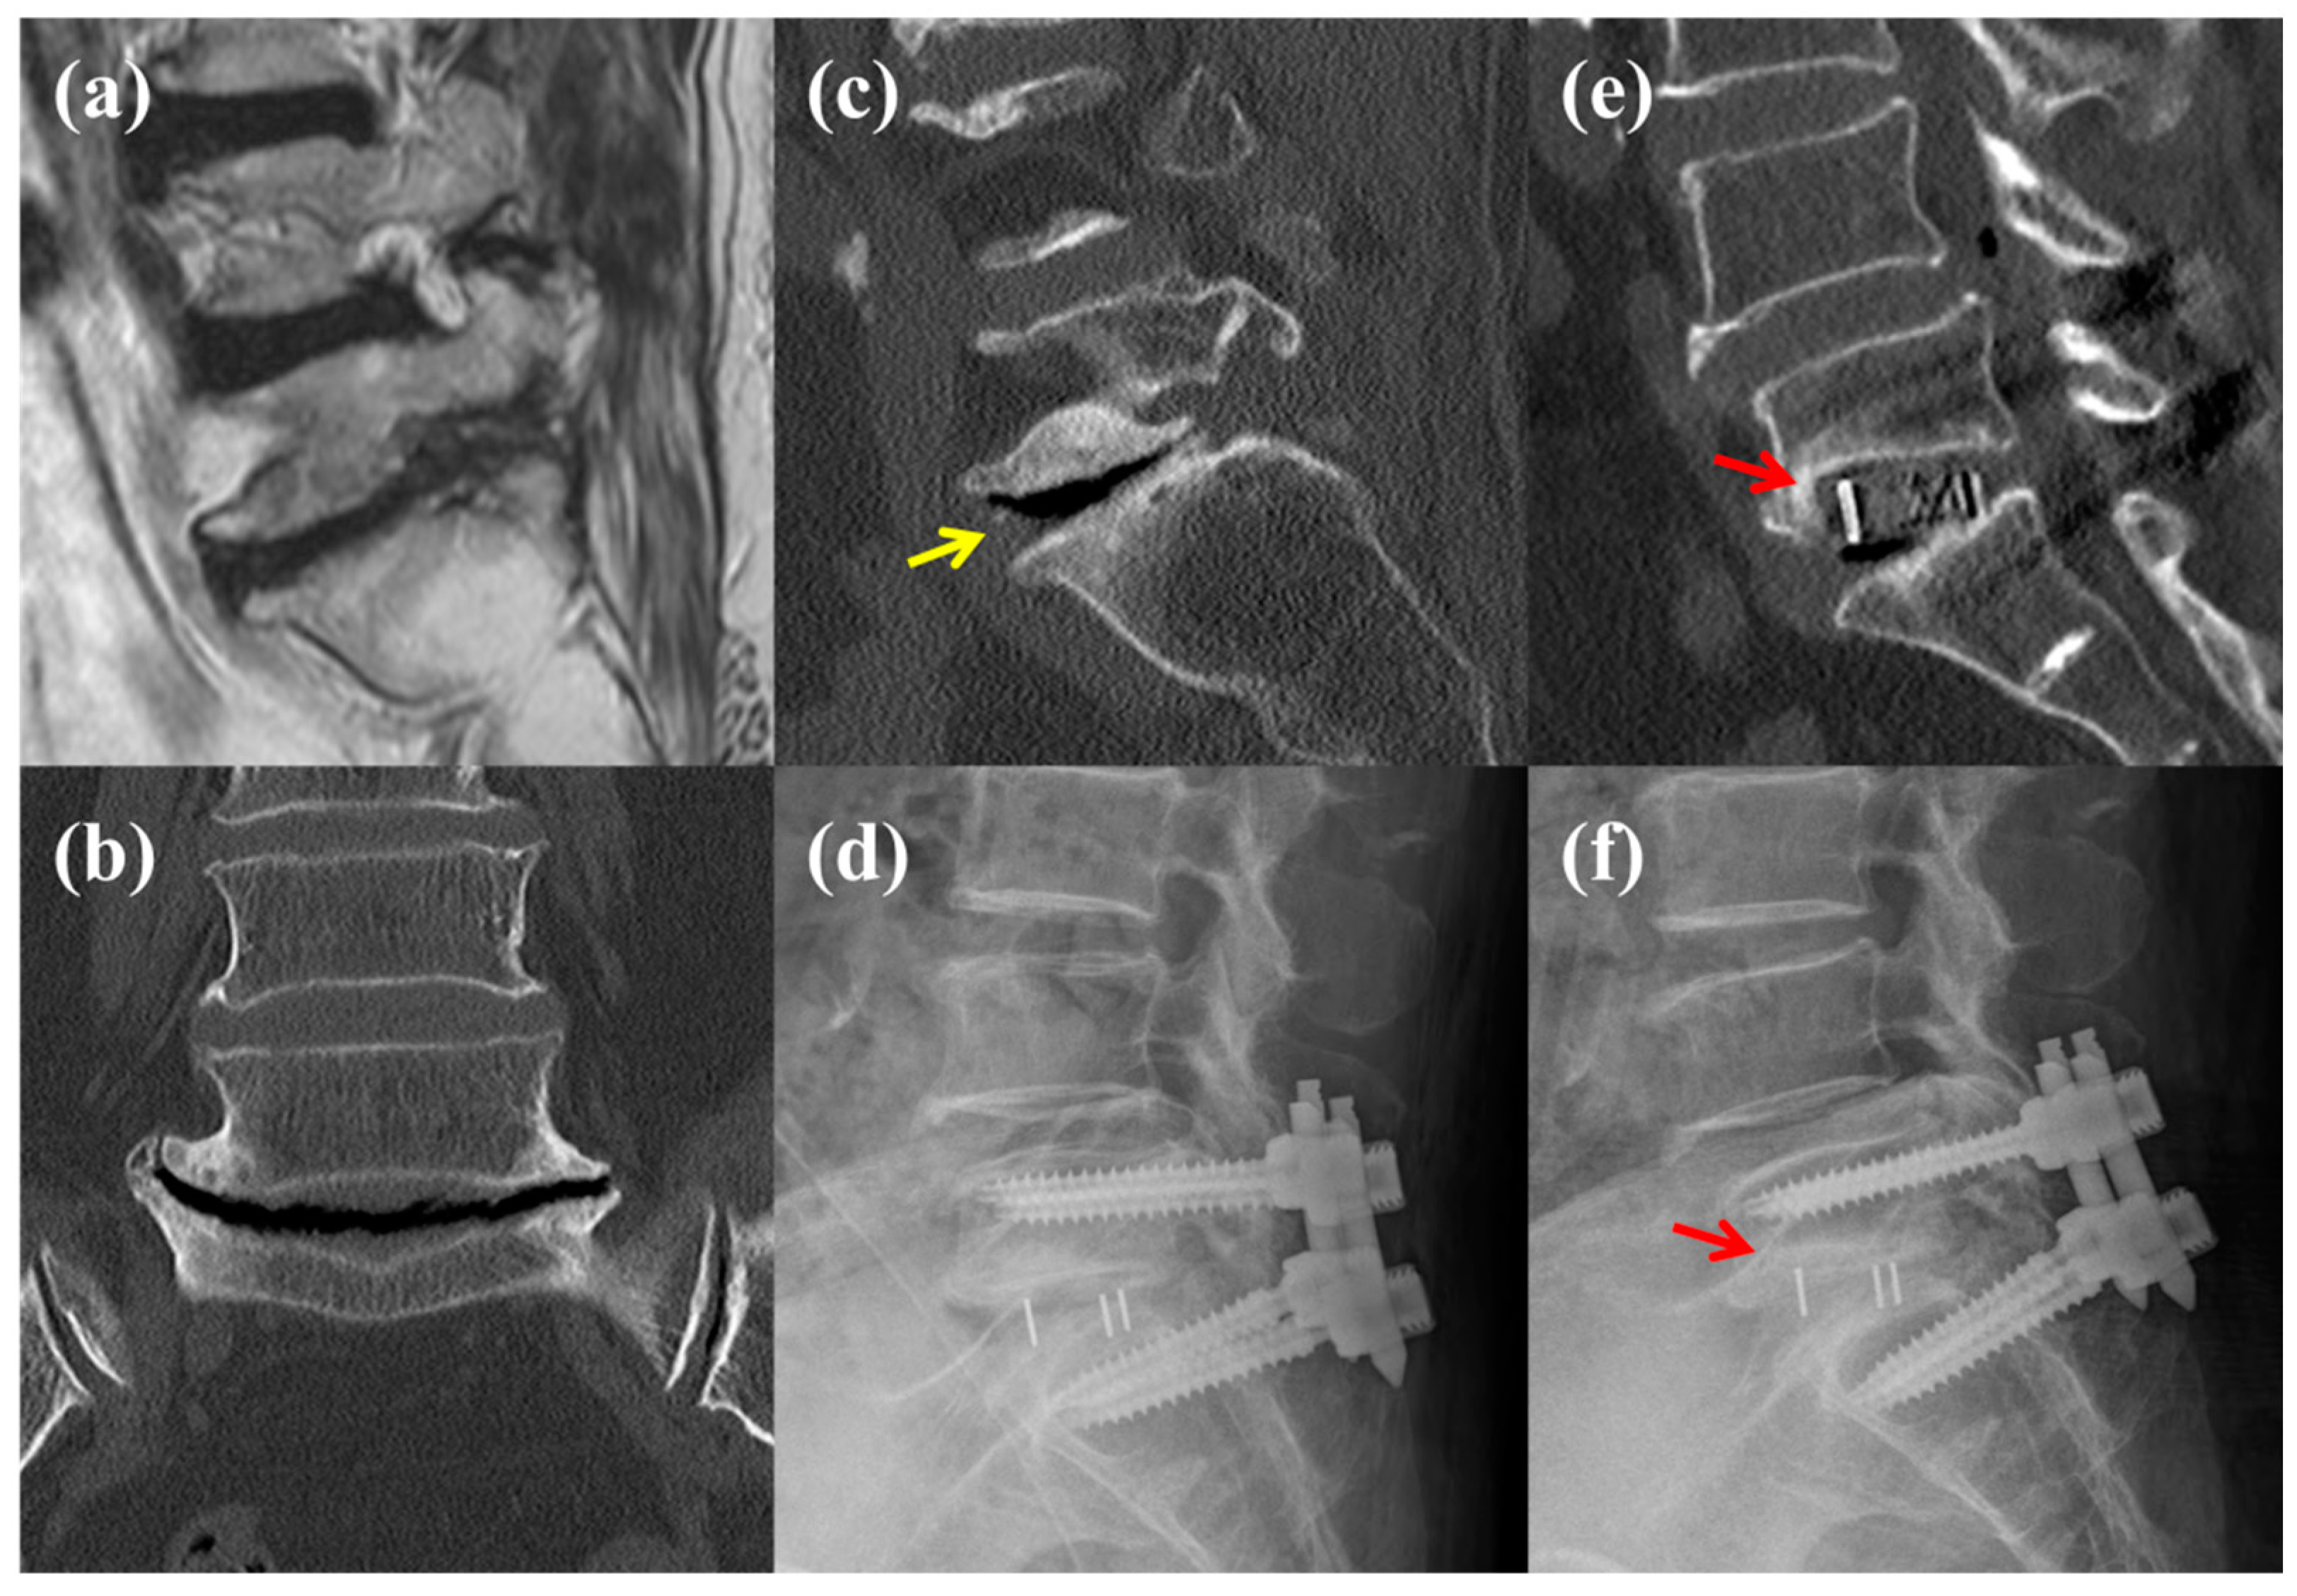

The "hoover" finding seen seen in joints that help differentiate degeneration from infection (esp. post surgical).

What is a vacuum cleft?